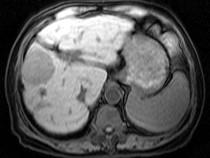

问题 男40岁肝区疼痛,消瘦乏力,腹部包块,AFP阳性,MR检查如图,最佳的诊断是哪一项()

选项 A.肝脓肿 B.肝血管瘤 C.肝腺瘤 D.肝肉芽肿 E.肝癌

答案 E